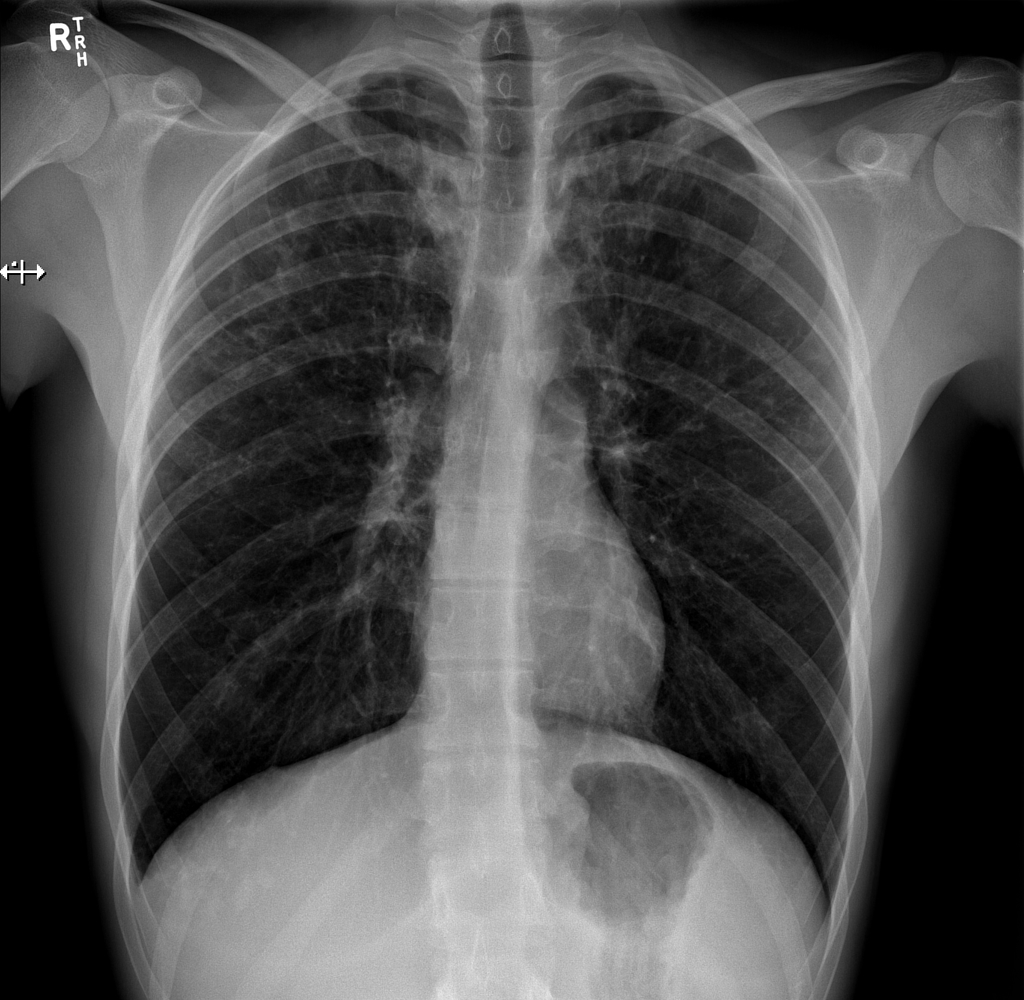

HOMEM, 50 ANOS, INTERNADO POR DISPNEIA + HEMOPTISE DE INÍCIO SÚBITO

áreas de opacidade em vidro fosco associadas a espessamento de septos interlobulares e intralobulares

HEMORRAGIA PULMONAR